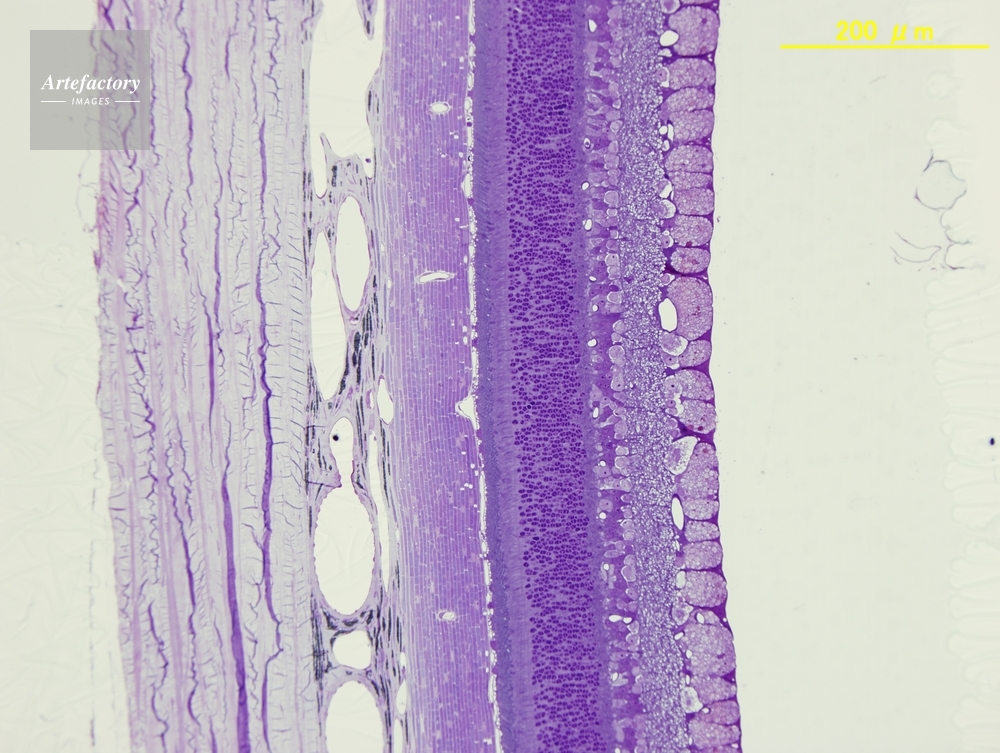

| 作品タイトル | ネコ,網膜 | モデルリリース | なし | |

| 作家 | OLYMPUS CORPORATION Technolab | プロパティリリース | なし | |